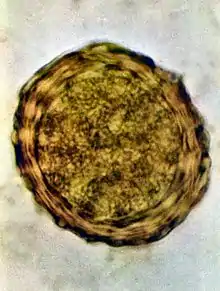

Ascaris lumbricoides is characterized by its great size. Males are 2–4 mm (0.08–0.2 in) in diameter and 15–31 cm (5.9–12 in) long. The male's posterior end is curved ventrally and has a bluntly pointed tail. Females are 3–6 mm (0.1–0.2 in) wide and 20–49 cm (7.9–19 in) long. The vulva is located in the anterior end and accounts for about one-third of its body length. Uteri may contain up to 27 million eggs at a time, with 200,000 being laid per day. Fertilized eggs are oval to round in shape and are 45–75 μm (0.0018–0.0030 in) long and 35–50 μm (0.0014–0.0020 in) wide with a thick outer shell. Unfertilized eggs measure 88–94 μm (0.0035–0.0037 in) long and 44 μm (0.0017 in) wide.[8]